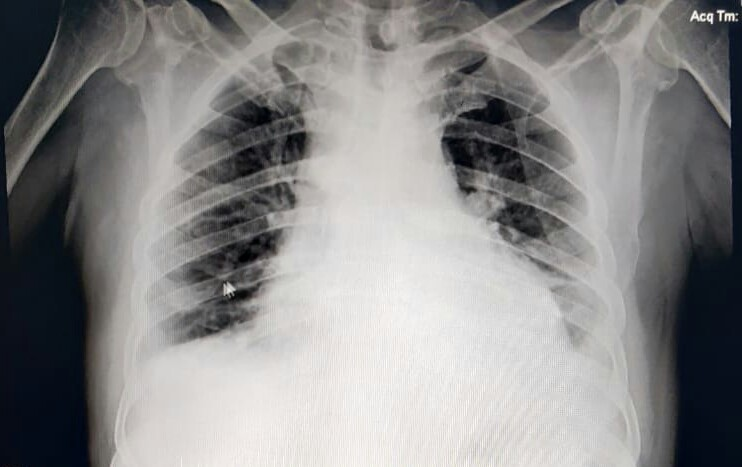

X- RAY CHEST

XRAY CHEST :

showing minimal effusion on left side